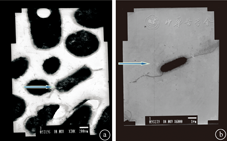

于肝螺杆菌感染后不同时间,分别取BALB/cCr小鼠肝脏组织行肝螺杆菌分离培养及Warthin-Starry嗜银染色,分析肝螺杆菌感染不同时间在小鼠肝脏组织的定植情况。结果显示,雄性BALB/cCr小鼠肝螺杆菌感染后3个月时在肝组织中即发现有肝螺杆菌定植,而雌性BALB/cCr小鼠在各个感染时间点肝组织中均未发现肝螺杆菌的定植。详见表1,图2,图3。

注:箭头所示为肝螺杆菌;a.短杆状菌体两端各有一个鞭毛(透射电镜×30 000);b.短杆状菌体两端各有一个鞭毛(扫描电镜×6 000)

注:a.感染3个月时小鼠肝细胞周围间隙内可见S状或短杆状菌体;b.感染6个月时小鼠肝组织汇管区周围可见S状或短杆状菌体